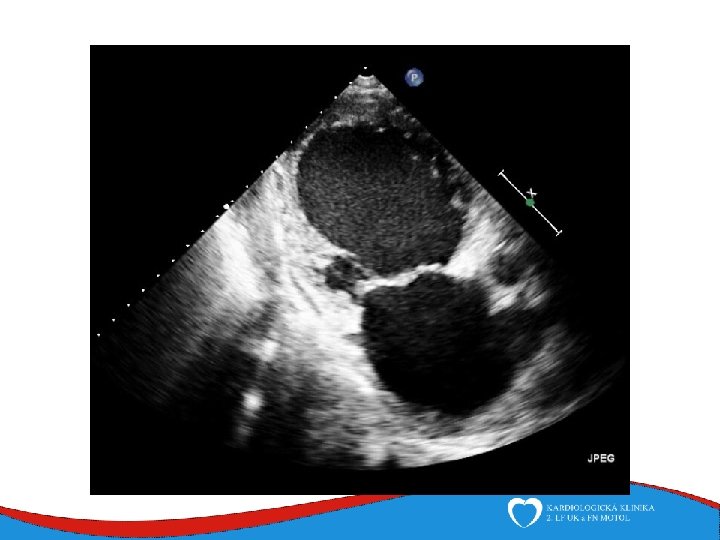

Patology and patophysiology Myocytal malfunction (atrophy/hypertrophy) Instersticial fibrosis → impaired systolic and diastolic function → compensatory mechanisms Dilatation (escpecially LV) - diffuse, RV (x CAD) Low CO, congestion Mitral regurgitation, secondary

Signs, symptoms and diagnostics • Heart failure- low CO, congestion • Arrhythmias • Sudden death • SVT, AF- mitral regurgitation- atrial dilatation • Thrombi in left ventricle/ left atrial appendage – CMP • ECG • ECHO – ventricular dilatation and dysfunction • Lab – NT-pro. BNP • Selective coronarography- CAD exclusion • Stress test- prognosis • MRI • EMB– inflammatory CMP